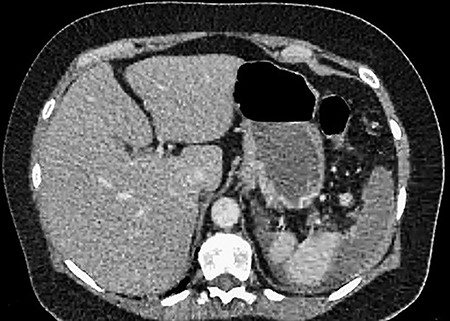

A 61-year-old female presented to a regional hospital with a 3-week history of intermittent diarrhoea, vomiting and generalized abdominal pain. She had a diffusely tender abdomen but was not peritonitic, and was shocked with a heart rate of 110 beats per minute, blood pressure of 89/45 mmHg and was peripherally cool. Her blood tests revealed a lactate of 7.2 mmol/L, which worsened to 7.8 mmol/L during resuscitation with intravenous fluids, and white cell count was 30.9 × 109/L, with an international normalized ratio (INR) of 1.4. She had an acute kidney injury with a creatinine of 119μmol/L and estimated glomerular filtration rate (eGFR) of 43 mL/min/1.73m2. Computed tomography (CT) revealed extensive thickened loops of non-enhancing small bowel with pneumatosis, moderate free fluid and a large splenic infarction. There was extensive thrombosis of the splenic vein and superior mesenteric vein extending into the portal vein to the level of the porta hepatis. Her background history included factor V Leiden and protein S deficiency, for which she had been non-compliant with warfarin during this illness. She had no surgical history (Figs. 1–5).

CT showing multiple thick-walled, non-enhancing loops of small bowel.

CT showing complete occlusion of the portal vein at the level of the porta hepatis.